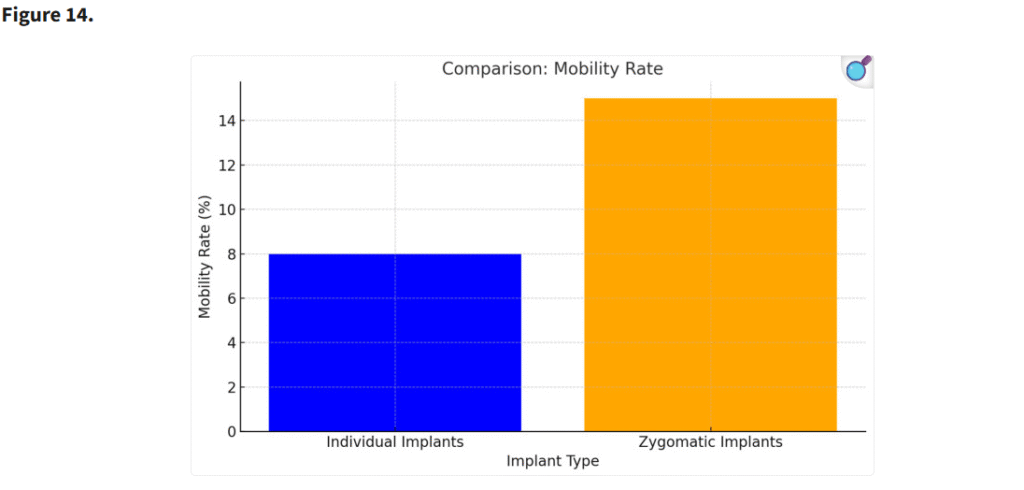

3.6. 炎症およびインプラントの動揺

個別設計インプラントを使用した患者では、ザイゴマインプラントと比較して炎症およびインプラントの動揺が著しく低かった。個別インプラントの高い安定性と生体適合性が、これらの合併症の軽減に寄与したと考えられる(p < 0.05)(Figure 14)。

ザイゴマインプラントのザイゴマ骨への固定は、カンチレバー効果を生じさせる。その結果、歯科用器具で圧力を加えた際に、ザイゴマインプラントの遠位端で動揺が顕著となる。(p < 0.05)